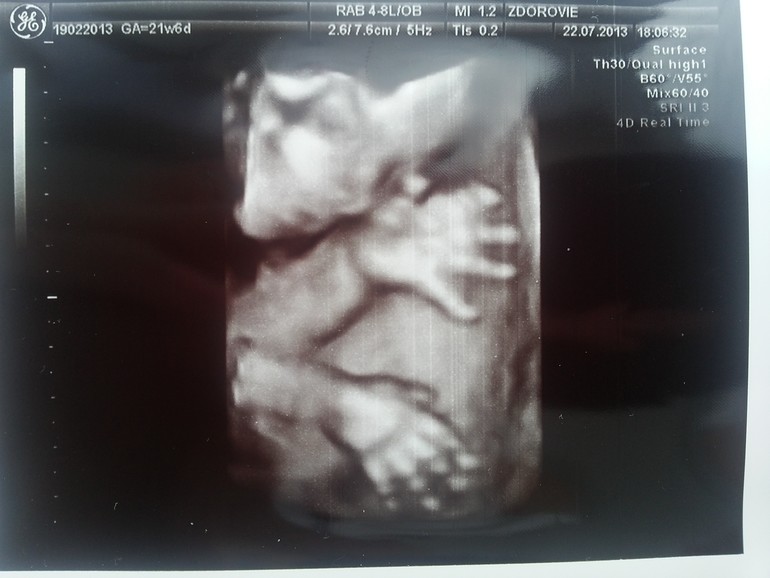

А вот и на фото наша малышка, лежала спокойно) пока ее рассматривали, на одной фотографии даже язык нам показала )))

Вот-вот, она язычок показывает )